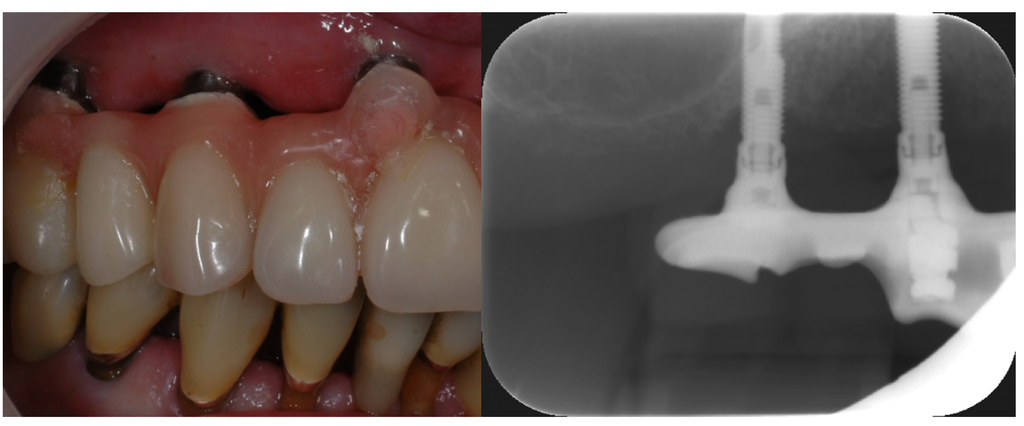

Figure 4. Secondary caries at the crown margin (black arrow) caused by accumulation of biofilm in the crevice between crown and tooth. Hyperplastic gingiva (white arrows) due to increased plaque accumulation in the connector area of the fixed partial denture. The connector area of the bridge has a bulky design which complicates interdental hygiene (photo: Marit Øilo).

Dental restorations affect the composition of the biofilm in many ways. There will always be steps, gaps or groves between tooth and restoration (Figure 3). These will complicate mechanical biofilm removal and alter the chemical balance in the biofilm in the region (Figure 4) [29,30]. Restorations differ from enamel with regard to surface roughness, surface energy and chemical composition [29,30,31,32,33]. Most adults have at least one dental restoration and the role of biofilm related infections related to the restoration as opposed to primary oral infections is not easily distinguished.